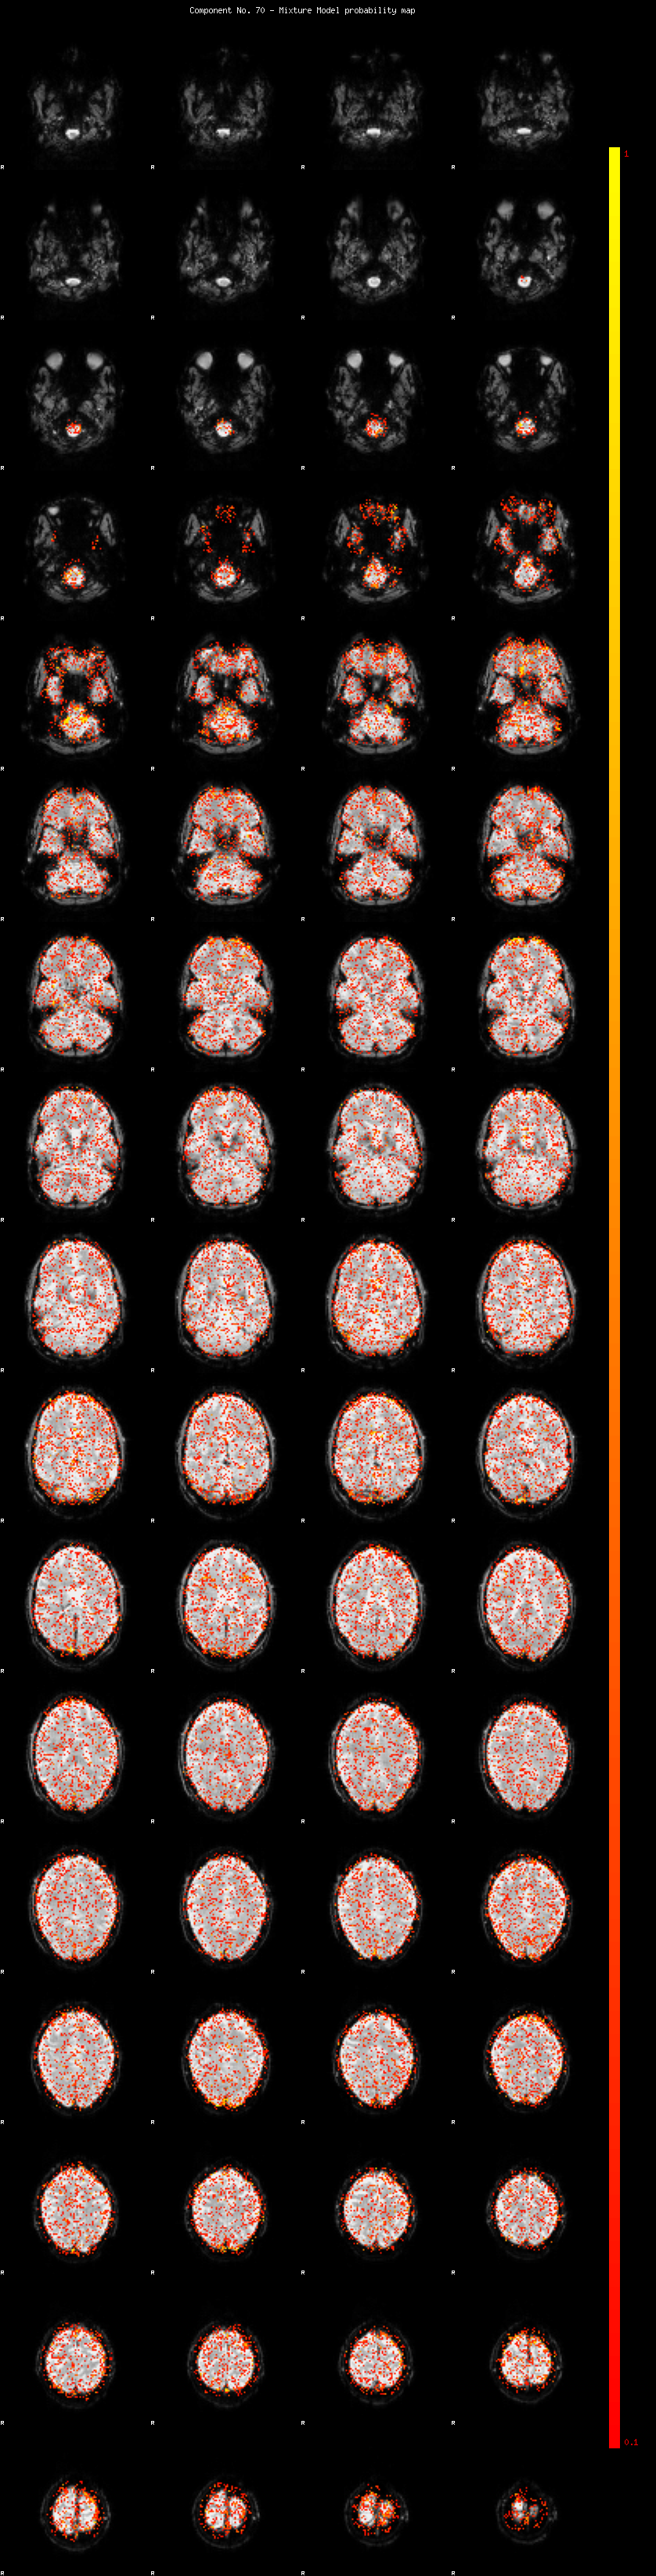

IC_70 Mixture Model fit

Means : 0.000000 1.999290 -2.003993

Vars : 1.000000 0.657115 0.672627

Prop. : 0.930580 0.036421 0.032999